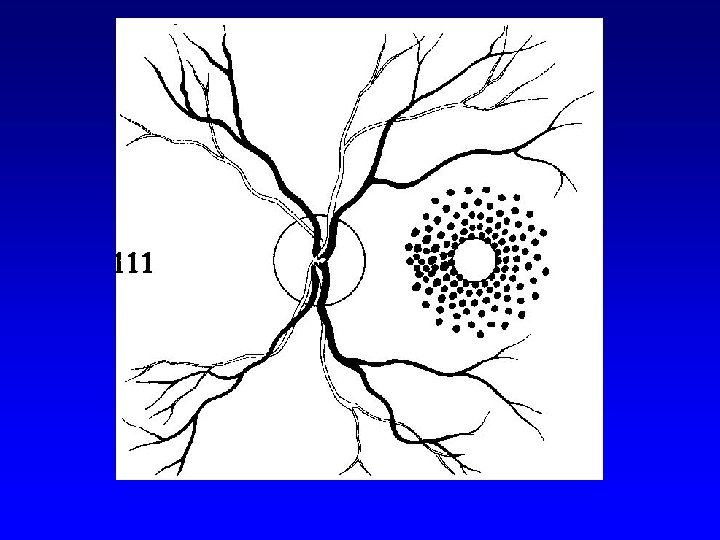

Laser therapy (technique) • Laser therapy of DR 1. focal 2. panretinal (scatter)

Laser therapy (technique) • Laser therapy of diabetic maculopathy 1. focal 2. grid

Grid laser